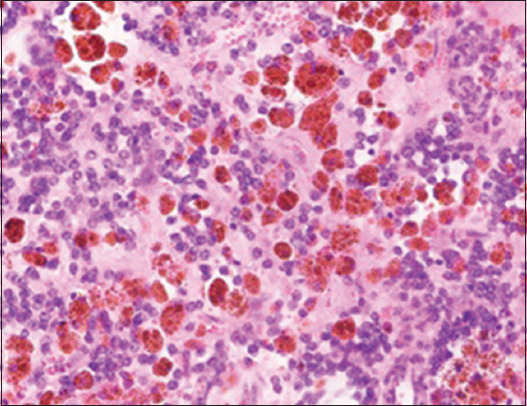

Case description: We present two pediatric cases of renal Ewing sarcoma. Both cases emphasize the significance of accurate diagnosis, multimodal treatment, and long-term follow-up in achieving favorable outcomes. Accurate diagnosis of renal Ewing sarcoma is crucial for effective management. Multimodal treatment involving neoadjuvant chemotherapy, surgical resection and staging with lymph node sampling, and chemotherapy continuation has shown promising results in our cases. Long-term follow-up is essential for monitoring disease progression and ensuring optimal outcomes.